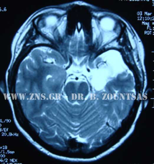

ΑΜΥΓΔΑΛΟΪΠΠΟΚΑΜΠΕΚΤΟΜΗ αριστερά